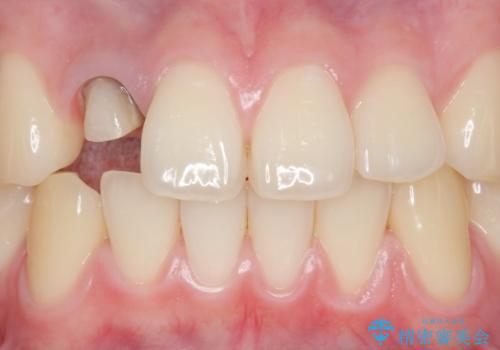

- 他院で入れたセラミッククラウンの色が気に入らないことを主訴に来院された患者様です。

高校生の時に部活で前歯をぶつけて神経が死んでしまい、歯が黒く変色したためセラミッククラウンで治療したとのことでした。

精査したところ、透過性のあるセラミッククラウンで治療されており、内側の黒い土台が透けてクラウンが黒ずんで見えていました。

土台を白いファイバーコアにやりかえたのち、土台の色を透過させないジルコニアフレームを用いたセラミッククラウンによる治療を行いました。